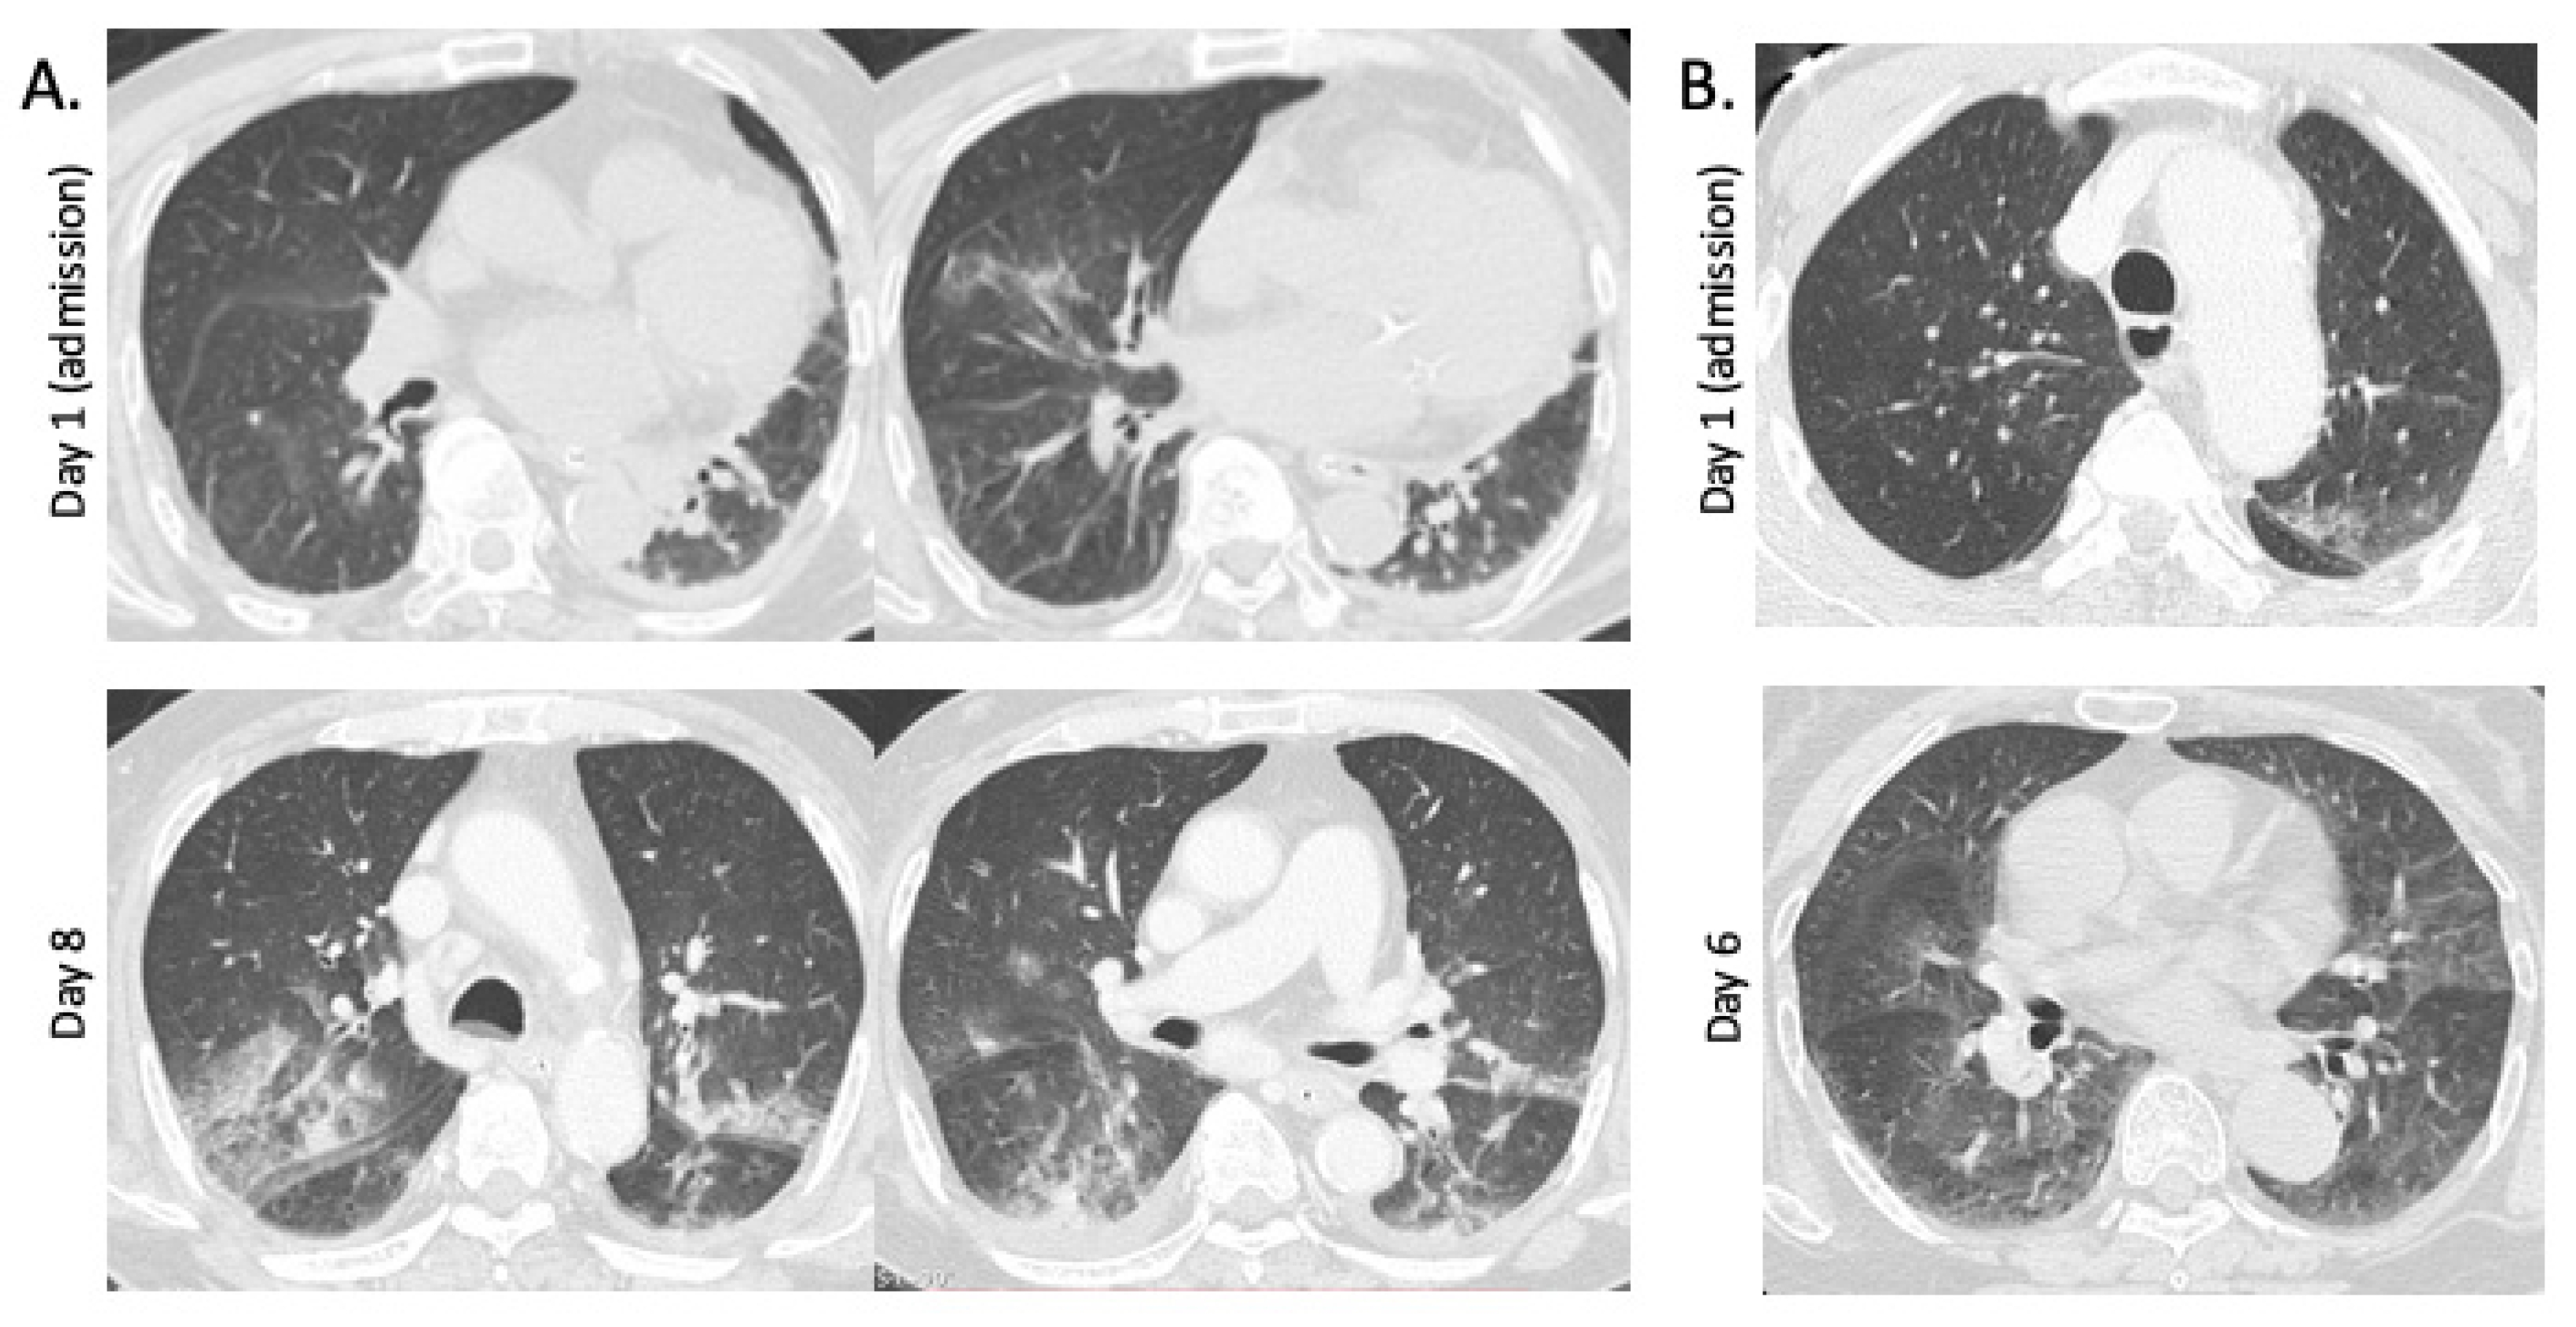

3.1. Chest CT Findings in Fatal and Non-Fatal Hospitalized Patients with SFTS